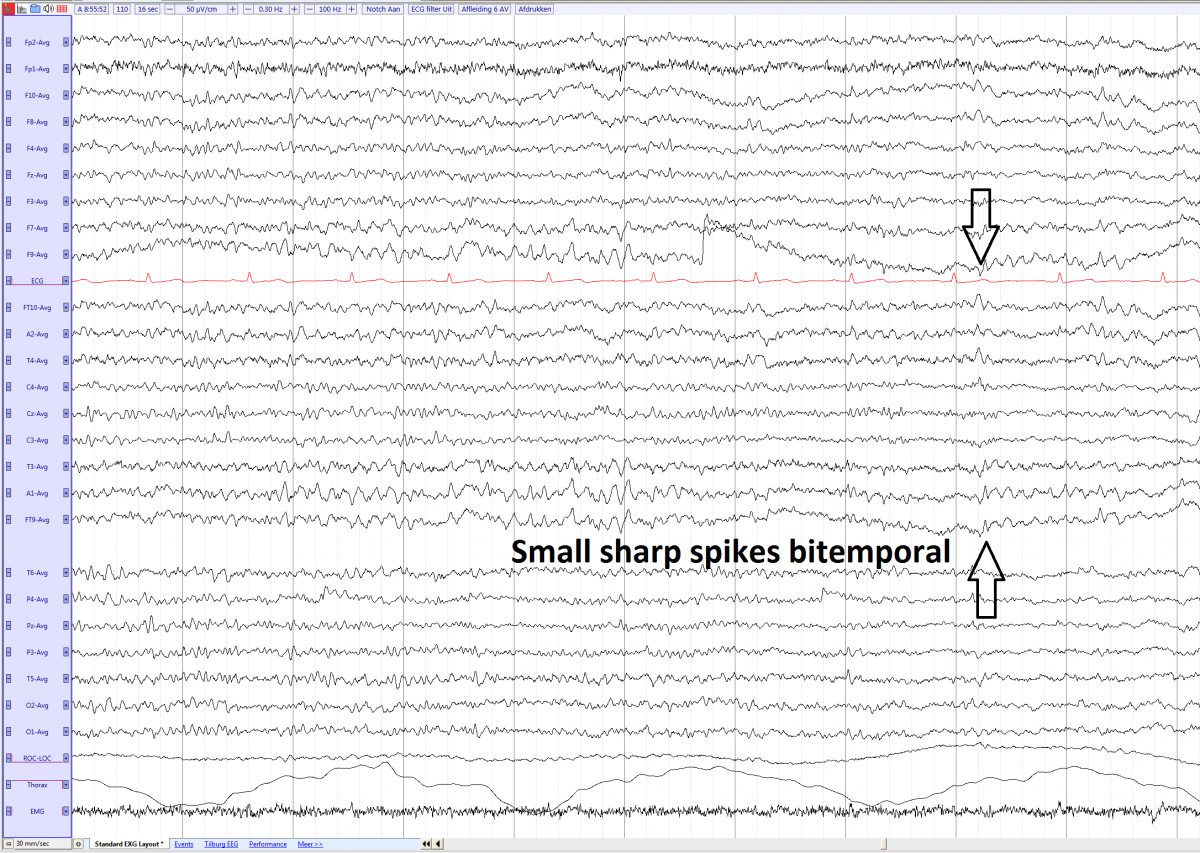

Small sharp spikes (SSS) Synonymes: BETS (Benign Epileptiform Transients of Sleep) and bening sporadic sleep spikes

• Occur in light sleep (non-REM 1 and 2 sleep)

• Amplitude of <50 microV and duration of <50 ms

• Usually monophasic, occasionally diphasic

• Occasionally followed by a slow wave, however do not disturb the background

• Located temporal uni- or bilateral

Small sharp spikes bilateral during non-REM 1 sleep (average)